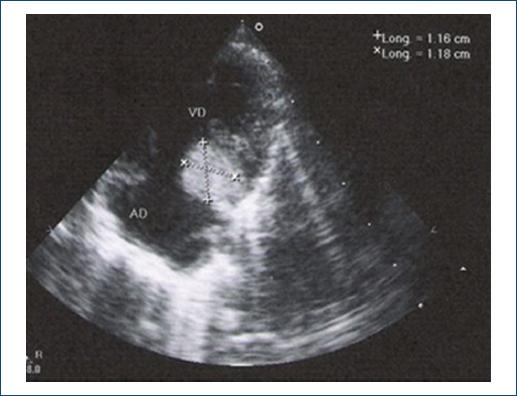

El estudio de imagen que se utilizó para confirmar el diagnóstico del tumor fue la ECOTT (Fig. 3). En 5 pacientes se confirmó por estudio histopatológico.

Figura 3 Imagen ecocardiográfica mostrando un engrosamiento en proyección posterior el cual corresponde a un rabdomioma.